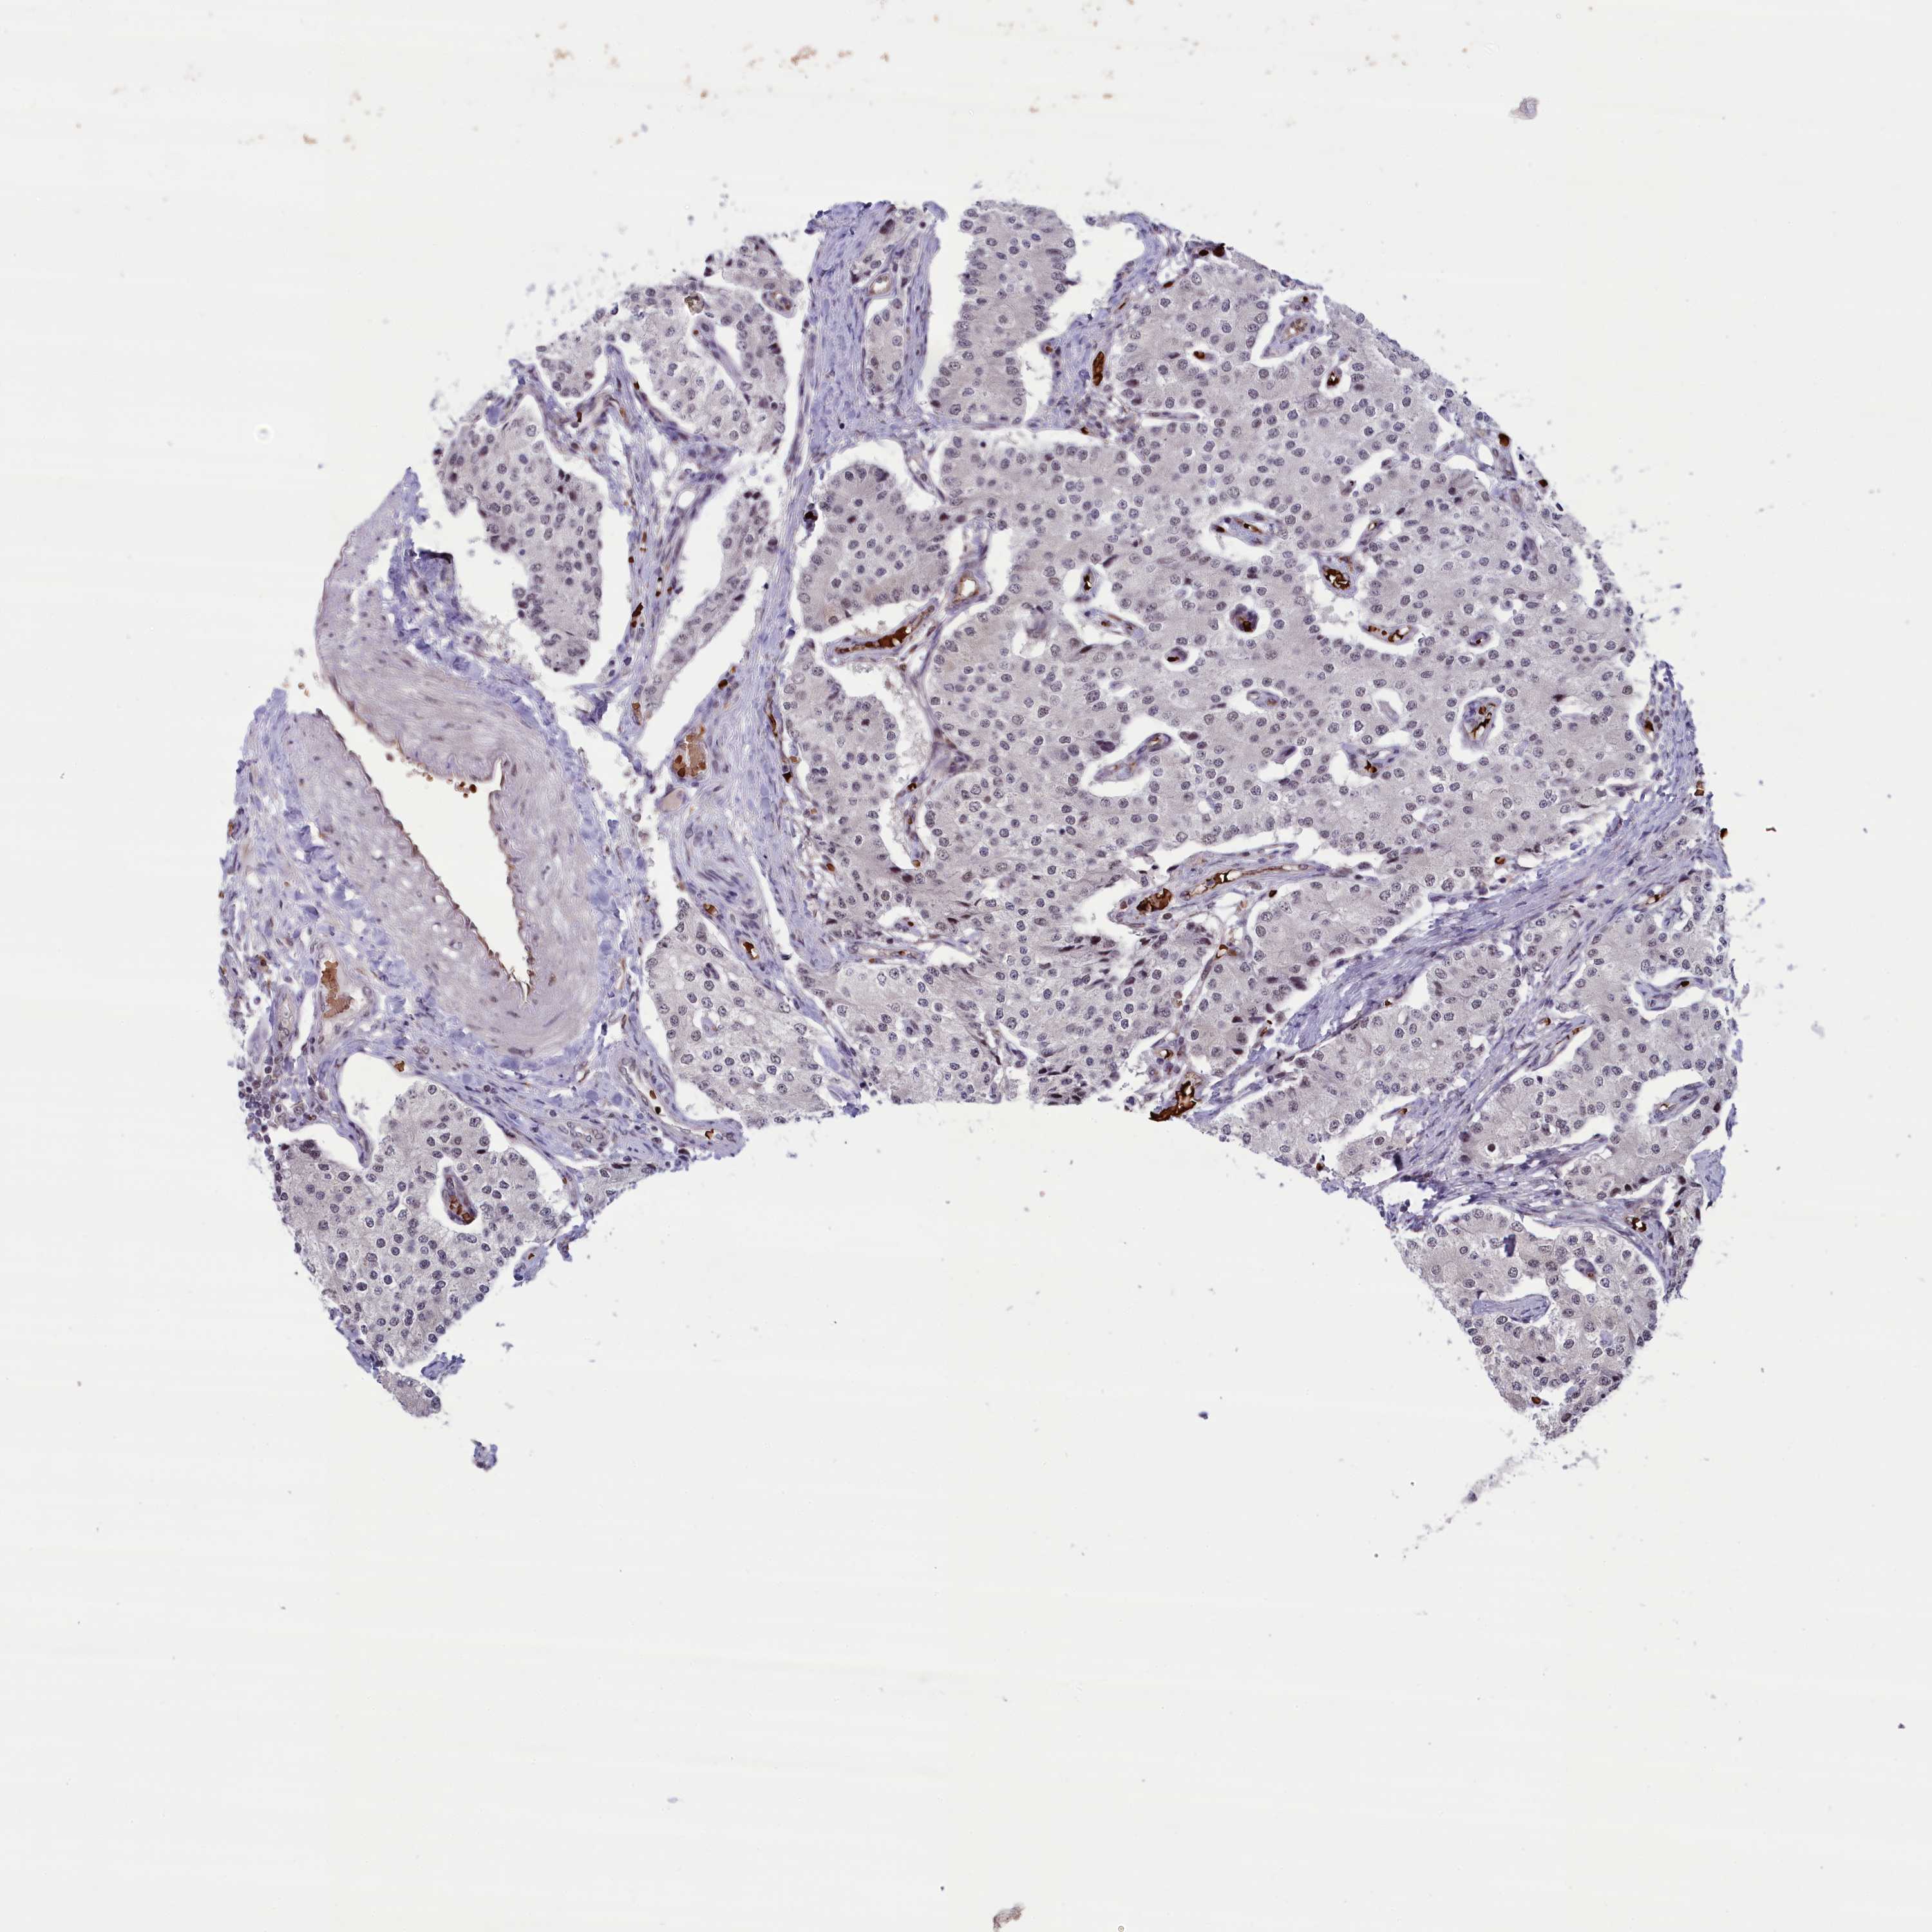

PATHOLOGY

CARCINOID

Neuroendocrine tumors

Human pathology